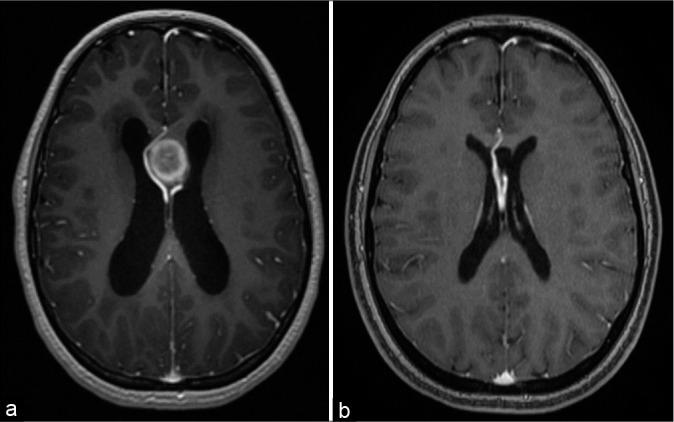

A 16-year-old girl presented with a 1-month history of gradual visual deterioration in the left eye, intermittent headache, and vomiting. Brain imaging showed hematoma located between the leaflets of the septum pellucidum with obstructive hydrocephalus. Transcallosal resection of interventricular mass was done. The patient was discharged with improved neurological symptoms; however, the left eye vision did not recover. Imaging demonstrated a unique anatomical variant in deep vascular structures.

一名16岁女孩,有1个月左眼视力逐渐下降、间歇性头痛及呕吐病史。脑部影像学检查显示血肿位于透明隔小叶之间并伴有梗阻性脑积水。行经胼胝体间脑室内肿物切除术。患者出院时神经症状改善;然而,左眼视力未恢复。影像学显示深部血管结构存在一种独特的解剖变异。